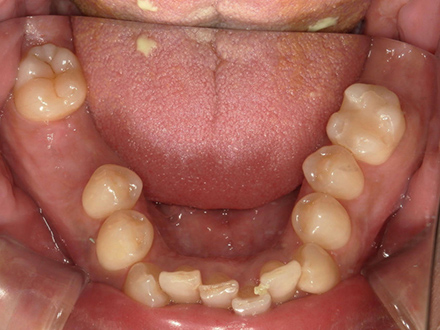

| 治療部位 | 両側下顎臼歯部 |

|---|---|

| インプラント本数 | 1本ずつ |

| 単価 | 40万円/本 |

| 合計費用 | 40万円 |